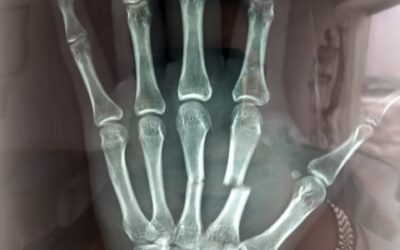

Urgencia, extrangulamiento en cuarto dedo por anillo

Paciente femenino de 45 años de edad, la cual acudió al servicio de urgencias con un anillo de acero el cual le extrangulaba el cuarto dedo. Se cortó el anillo con pinzas corta clavo de Steinman...